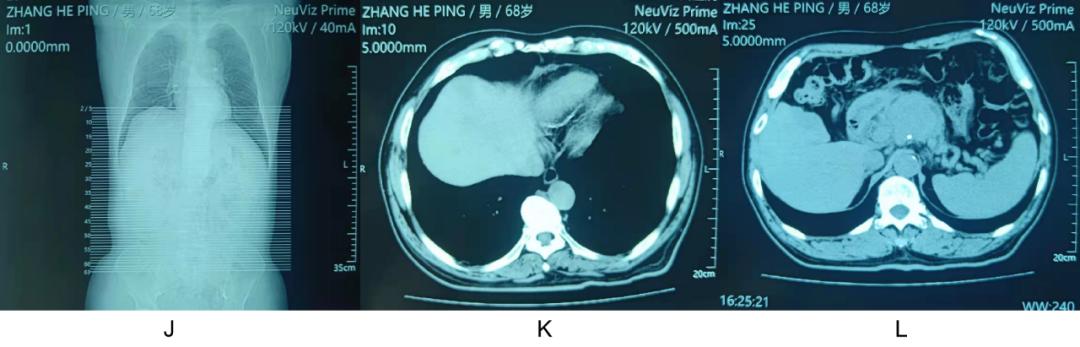

男,68 岁,发热,胰头癌肝多发转移,肺部 CT 正常,经美罗培南 + 阿米卡星治疗无效,因美罗培南及阿米卡星在胆汁里浓度不高,又换成头孢哌酮舒巴坦 + 左氧氟沙星治疗,仍无效。家属把腹部 CT 及核磁邮寄到北京请专家看过后建议替加环素治疗。我会诊后建议停用目前所有抗生素,调整为青霉素 480 万单位,q6 h静点,当晚就开始不再发热,病人自诉全身非常舒服。

注: J:右侧膈肌向上隆起,可见两处隆起,提示占位;K:肝右叶前段隆起,有一低密度占位;L:胰头占位。

【点评】

肝多发转移瘤病人发热,考虑肝内胆管引流不畅而细菌感染发热,国外 胆源性肝脓肿的细菌概率统计表明大肠埃希菌是第一位的,草绿色链球菌是第二位的 ,当美罗培南 + 阿米卡星治疗无效时说明致病菌是大肠埃希菌的可能性很低,换为头孢哌酮舒巴坦 + 左氧氟沙星是没有多大意义的,而某专家的建议显然也没有针对性,草绿色链球菌对青霉素几乎都是敏感的。这一例提示我们抗生素的使用需要对感染部位的常见细菌要熟悉。